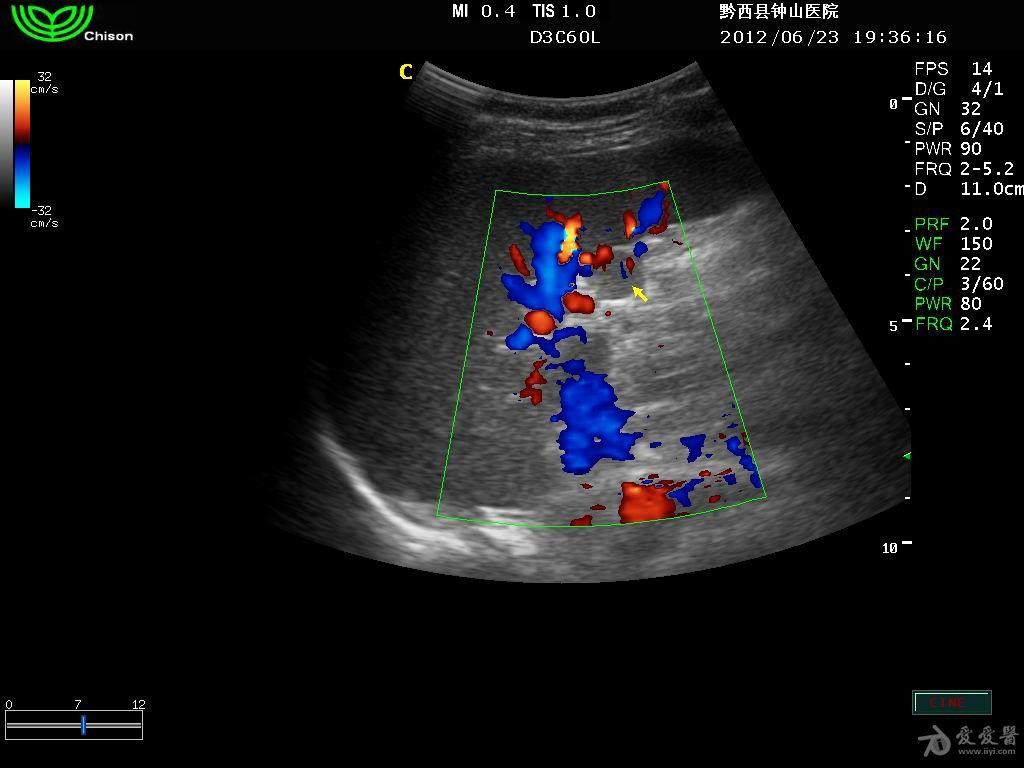

副脾彩超报告

副脾彩超报告,副脾超声报告

临床资料:女,54岁,常规体检.超声综合描述:脾厚3.3cm

副脾彩超图片